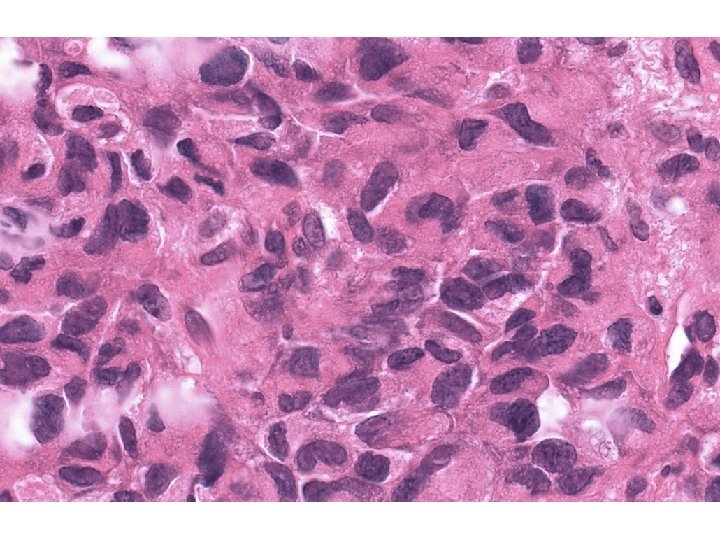

Histopatologický nález • Tumor: ložiskovitě nekrotizující a prokrvácené tumorosní masy tvořené buněčnými skupinami a

Histopatologický nález • Tumor: ložiskovitě nekrotizující a prokrvácené tumorosní masy tvořené buněčnými skupinami a pruhy větších polygonálních až vřetenitých buněk vykazujících cytonukleární polymorfismus i mitotickou aktivitu. • Linea serrata: lymfoplasmocytární zánětlivá infiltrace sliznice subepiteliálně, s úseky úplné intestinální metaplasie epitelu – Barrettův jícen.

? Nízce diferencovaný karcinom? Stromální tumor? Jiný tumor?